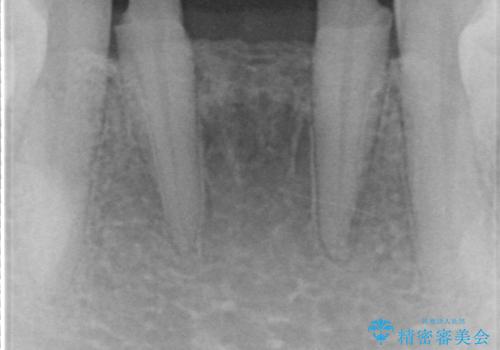

下の前歯のブリッジ 保険治療のやり替え

- 前歯のブリッジのやり替えをご希望されました。

かみ合わせが強く、以前入っていた保険治療のブリッジも前装が欠けてしまっていました。

セラミックも強い衝撃で欠けないわけではないため、強度のあるフルジルコニアクラウンでブリッジを作成しました。